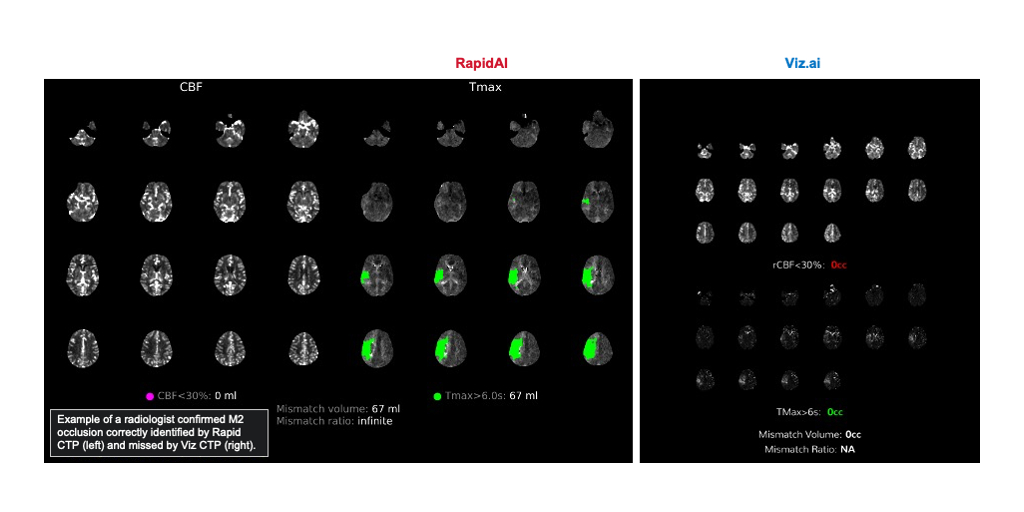

The data, presented as a late-breaking abstract at the European Stroke Organisation Conference (ESOC) 2025, analyzed 1,591 consecutive stroke cases at a comprehensive stroke center. Of the 1,122 eligible cases, RapidAI detected 93% (109) of MeVOs using CT Perfusion alone, compared to 70% (82) by Viz.ai.

MeVOs refer to occlusions in smaller, yet still crucial, arteries in the brain, such as the M2/M3 segments of the middle cerebral artery or the A1/A2 and P1/P2 segments of the anterior and posterior cerebral arteries. These blockages can cause severe damage if left untreated but are notoriously difficult to identify without high-performing imaging tools. The substantial number of MeVOs missed by the Viz.ai software could lead to significant delays in diagnosis and treatment.